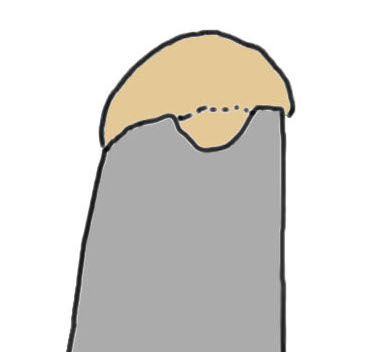

Small full thickness rotator cuff tear of supraspinatus - retracted to footprint